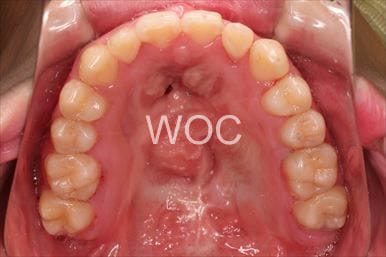

治療後1

-